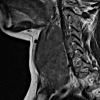

MRI of the thyroid gland.

Магнитно-резонансная томография щитовидной железы. Это метод исследования аппаратуры с использованием магнитного поля, используемый для изучения этого эндокринного органа. Магнитно-резонансная томография позволяет оценить расположение и размеры долей и перешейка железы, ее структуру. Кроме того, этот метод позволяет выявить наличие воспалительных процессов, опухолей, сдавление железы соседними структурами, изучить соседние органы и ткани. Как правило, магнитно-резонансная томография щитовидной железы является самостоятельной процедурой, которая выполняется естественным путем, однако при необходимости можно использовать более глубокий метод внутривенного контрастирования. Специальной подготовки больного перед прохождением исследования не требуется.